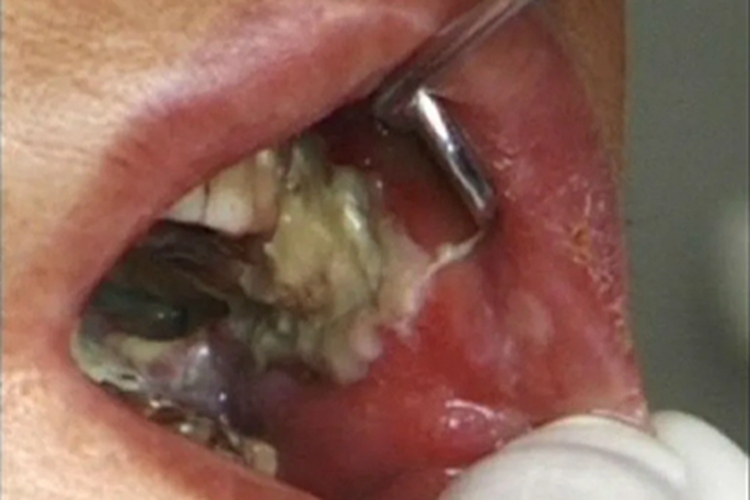

颊癌可发生在患者一侧颊黏膜表面,临床可表现为局部表面出现白斑,呈糜烂样改变,形状不规则,与周围皮肤的边界较为清晰,周围有炎性红晕,生长较快,容易向四周及深层组织浸润,部分患者可逐渐出现张口受限等情况。